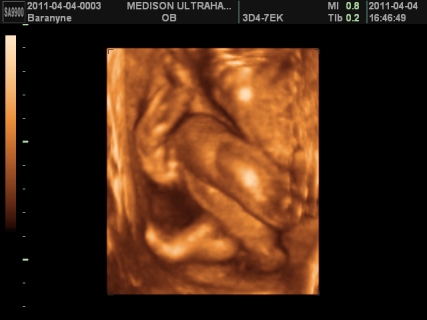

gyerek témában is helyretettem magam, ennek is tök egyszerű oka van, FÉLEK TŐLE. ezen nem változtat az idő, ha 1 év mulva mennék ,akkor is félnék tőle. sajnos nekem nem életem legszebb élménye volt a várandóság, én tényleg terhességként éltem meg. egyszerűen annyi a szabadságomnak, mert szinte mindenről le kell mondanom, bár remélem most nem így lesz meg. ámulva hallgatom, akinek a legszebb élmény a várandóság volt. valamilyen szinten nekem is, de csak mikor kiderült ,hogy sikerült és mikor megszületett boti, a többi rész kihagynám, mert nem tudtam önfeledten örülni sem az első szívhangnak, sem az első uh-nak, mert mindig bennem volt a félsz. ezt talán legjobban bibó értheti meg. viszont nagyon nagyon szeretnék egy kismanót, de egyszerűen nem tudom elképzelni, hogy hogy fogom tudni boti mellett megoldani. anyuékhoz sem passzolhatom le mindig botit, ha mondjuk fáradt leszek, vagy isten ne adja vérzek. mi lesz vele? na ezen ráérek agyalni, de már nem sokáig, mert kb 3 hét és visszaülti. bár tudnék felhőtlenül örülni, de a félelmemet nem tudom leküzdeni. alig várom ,hogy jöjjön a kisboti